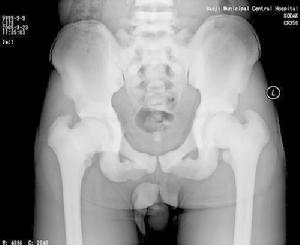

石骨症為全身性骨骼受累的疾病,顱骨的X線表現為硬化,尤以顱底為顯著,特別是蝶骨體及大、小翼均明顯改變。蝶鞍大小正常或縮小,床突、鞍底皆硬化。顳骨及枕骨也可硬化,使板障封閉,失去三層的分野。頂骨額骨及顏面骨可不受侵犯或僅有輕微變化。視神經孔變窄且邊緣模糊乳突小房及鼻旁竇變小或發育不全石骨症在長管狀骨及脊椎有特徵性的X線改變。脊椎椎體表現為上下緣特别致密,其間密度低者為正常骨質,組成三層帶狀影。長管狀骨表現為“骨內骨”,骨質緻密髓腔變窄或消失於乾骺部顯示多條互為平行或呈波狀緻密線紋,乾骺部可呈杵狀變形,尤其脛骨上端內側可表現為邊緣不整呈粗鋸齒改變,髂骨翼典型改變為平行髂嵴的多層的同心弧狀硬化帶此外,肋骨和鎖骨均可呈均勻硬化。有時還可見到骨折,於掌、蹠、指及趾骨常有界限分明的骨島出現。

(1)基本X線表現:廣泛均勻,骨密度增高硬化,骨小梁變粗、模糊,皮質增厚,髓腔狹窄,甚至消失。本院曾有3例石骨症病人,因發生骨折,欲行帶鎖髓內針固定,因髓腔消失,骨質硬化,改用鋼板或動力髁鋼板固定,骨密度增高有明顯的均勻對稱性,以四肢、肋骨和骨盆較明顯。

(4)髂骨翼年輪樣改變。射線可透過帶是較正常骨區域,而緻密帶存在大量不起作用的破骨細胞。

(5)顱骨穹窿顱底均增厚硬化,以顱底骨質增生最明顯。